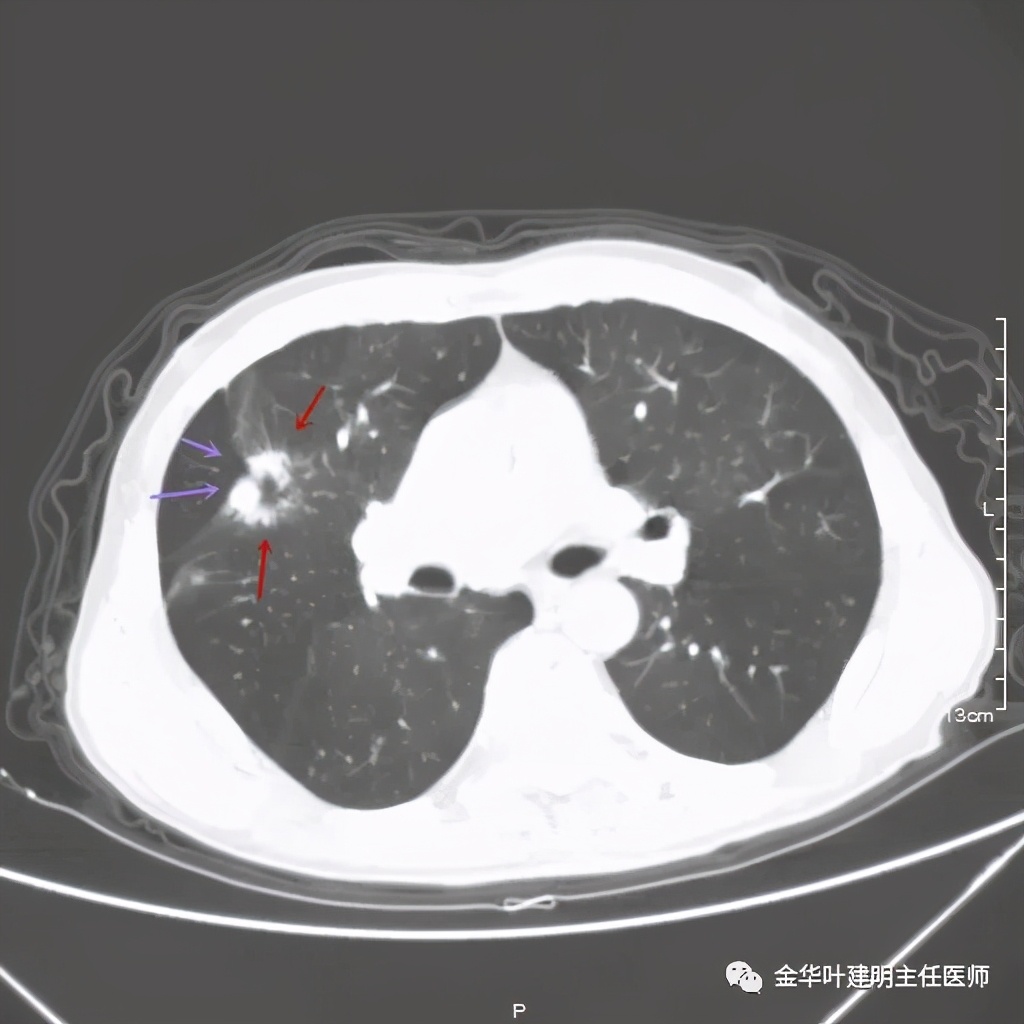

上图示病灶边缘不太光整,内部密度不太均匀

上图紫色箭头示叶间胸膜受牵拉,病灶边缘部分见到细毛刺

上图是穿刺时的某个层面,病灶的细毛刺征比较明显(蓝色箭头),病灶的边缘是不平的,而且有细短的毛刺样突向周围肺组织,这可是恶性的特征

上图紫色箭头示明显的叶间胸膜牵拉,红色箭头示病灶,中间还有空腔,边缘有细毛刺,感觉上病灶就是有收缩力而僵硬的

上图也见细毛刺,但不是特别广的范围,有的边缘还是相对比较光滑了点